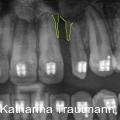

Die interdisziplinäre Zusammenarbeit spielt in der modernen Kieferorthopädie eine zentrale Rolle, insbesondere bei komplexeren Behandlungsfällen, die über das alltägliche Behandlungsspektrum hinausreichen. Fotos: © Dr. Johanna Katharina Trautmann